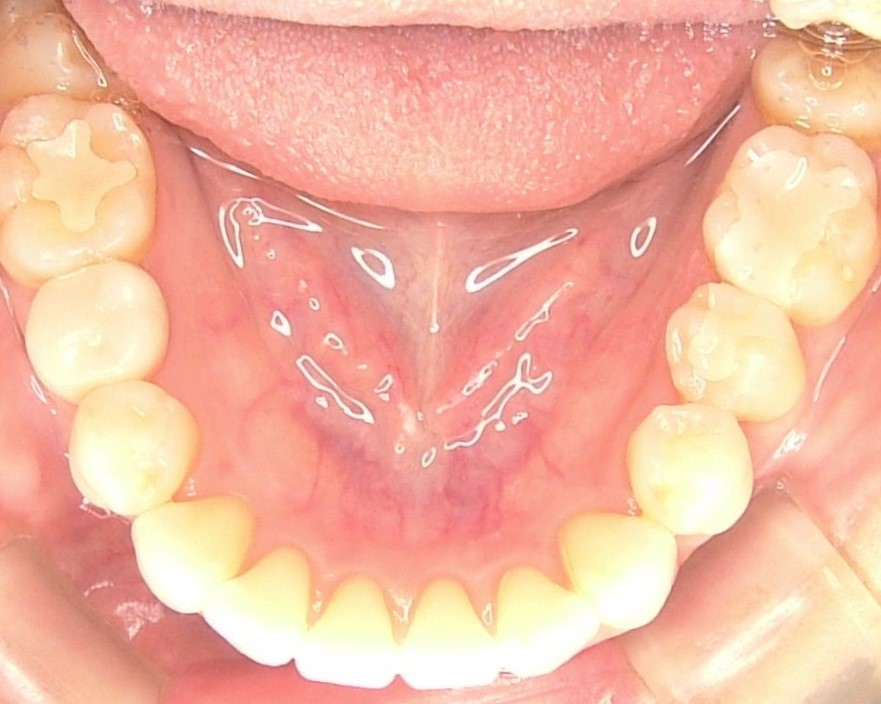

初診時 |

口腔内写真 |

| 治療内容 | 掌蹠膿疱症、不定愁訴も治したい。花粉症もあり。ガルバニー電流測定、オリゴスキャン検査、ビタミンDの血中濃度測定 |

|---|---|

| 治療期間・回数 | 5か月・30回 |

| 治療時の費用 | 1,200,000円(メタルフリー代、サプリメント代) ※本症例当時の価格です。最新の費用はこちら |

| リスク・副作用 | 金属除去後に熱が出たそうですが、一時的な好転反応と思われます。このような症状は個人差があるので、特に心配はありません。 |